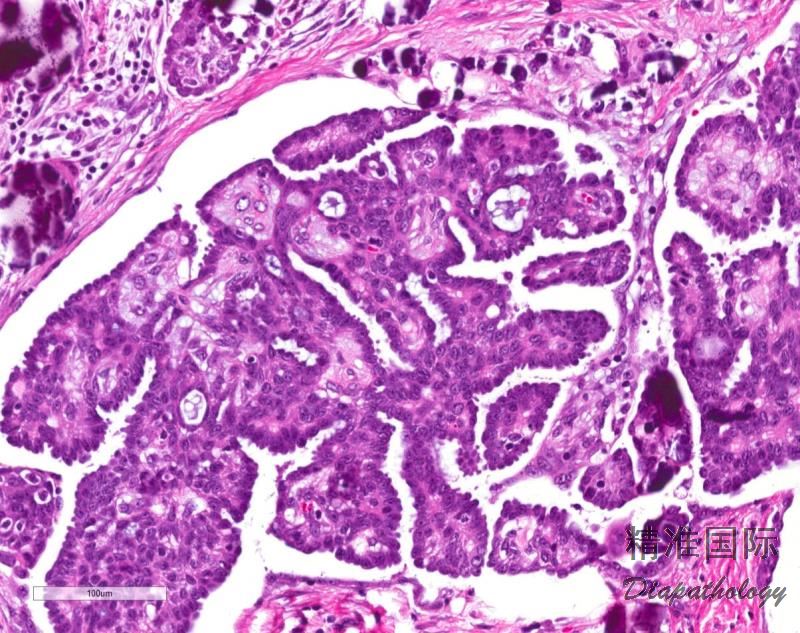

特征性改变是各种类型的间质浸润,如单个细胞、不规则小细胞巢杂乱浸润间质;微乳头或大乳头周围围以无上皮衬覆的空隙;不同浸润方式可同时存在;

细胞小,形态一致,核多形性不明显,仅轻度-中度异型,具有 1 个明显的核仁;

分裂象少,常小于 3 个/10HPF;

砂粒体常见。